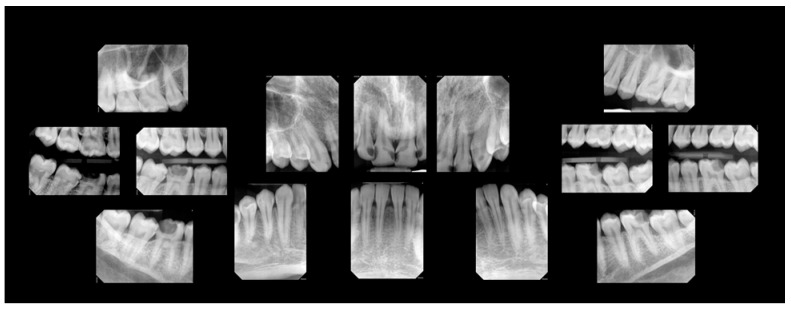

背景:在加拿大,尽管全民医疗保健,但牙科保健仍然主要由私人资助,造成了经济障碍,使许多人无法获得基本服务。这个案例研究是一个更大的倡议的一部分,一个微笑研究项目,该项目评估免费牙科护理对口腔健康和整体福祉的影响,这些人在过去两年中由于经济限制而无法获得牙科服务。该计划的参与者接受必要的牙科护理,并参加后续预约,以评估持续免费护理的长期效果。临床病例:这个混合方法的病例报告集中在一位26岁的男性参与者身上,并将定性的半结构化访谈与临床和自我报告的数据相结合,提供了对他的经历的深入了解。结果:临床结果证明了所提供的牙科治疗的有效性,而自我报告的措施表明改善了口腔健康,对牙齿外观的满意度,增强了心理社会健康,增强了自尊,减少了牙科焦虑,改善了口腔卫生习惯。定性访谈确定了反映该项目积极体验的三个关键主题:入学便利、员工友善和整体幸福感的提高。定量和定性分析的结合表明,在客观和主观措施方面,特别是在总体福祉方面,都取得了重大进展。结论:持续的免费牙科护理有效地解决了参与者的口腔健康和整体福祉,即使在两年的随访中,大多数益处仍在持续。这些个人水平的结果为加拿大医疗保健系统中全民牙科覆盖的潜在优势提供了初步的见解。

Background: In Canada, despite universal healthcare coverage, dental care remains predominantly privately financed, creating financial barriers that prevent many from accessing essential services. This case study is part of a larger initiative, the One Smile Research program, which evaluates the impact of cost-free dental care on the oral health and overall well-being of individuals who have been unable to access dental services in the past two years due to financial constraints. Participants in the program receive necessary dental care and attend follow-up appointments to assess the long-term effects of continuous cost-free care. Clinical Case: This mixed-methods case report focuses on a 26-year-old male participant and integrates a qualitative semi-structured interview with clinical and self-reported data, providing an in-depth understanding of his experiences. Results: Clinical outcomes demonstrated the effectiveness of the provided dental treatments, while self-reported measures indicated improved oral health, satisfaction with dental appearance, enhanced psychosocial well-being, increased self-esteem, reduced dental anxiety, and better oral hygiene habits. The qualitative interview identified three key themes reflecting positive experiences with the program: ease of admission, staff kindness, and overall well-being improvement. The integration of both quantitative and qualitative analyses revealed significant advancements in both objective and subjective measures, particularly regarding overall well-being. Conclusions: The continuity of cost-free dental care effectively addressed the participant's oral health and overall well-being, with most benefits sustained even at the two-year follow-up. These individual-level outcomes offer preliminary insight into the potential advantages of universal dental coverage within the Canadian healthcare system.